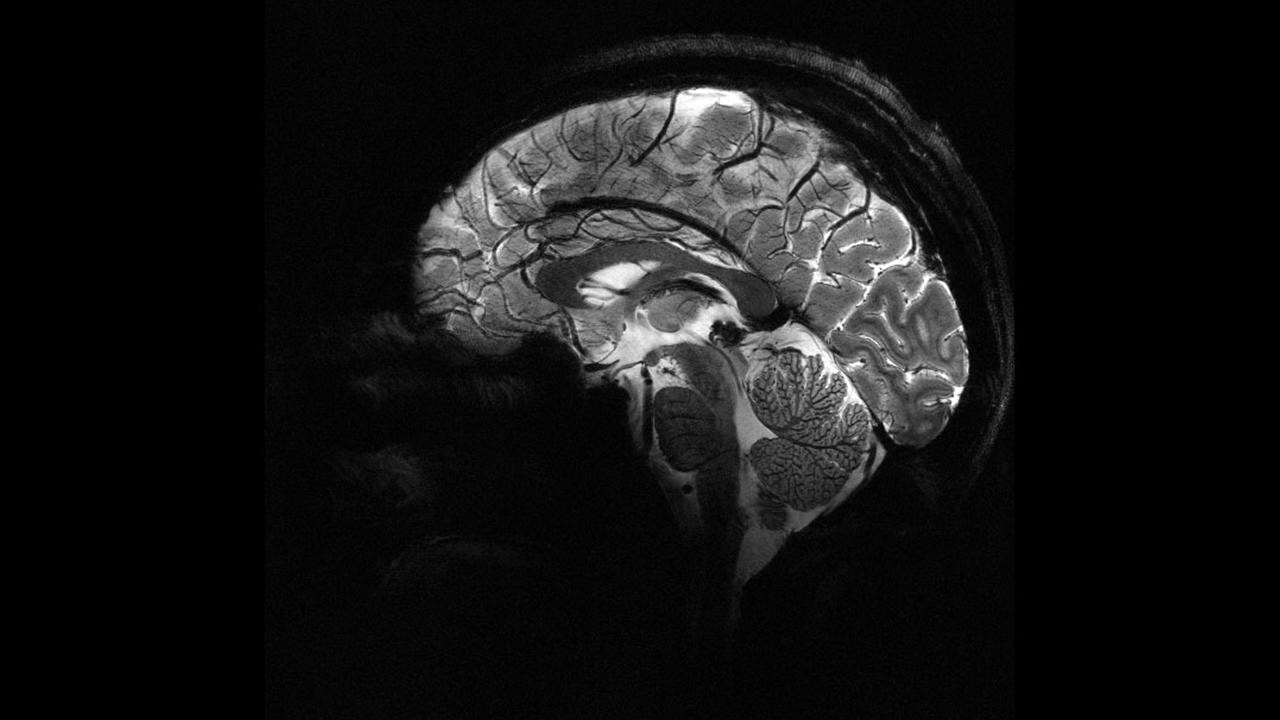

Pandemi beyinleri hızla yaşlandırdı

Yeni bir araştırmaya göre, COVID-19 döneminde insanların beyinleri 2020 öncesine kıyasla ortalama 5,5 ay daha hızlı yaşlandı. Üstelik bu artış, COVID'e yakalanmayanlarda da görüldü.

İngiltere'deki Nottingham Üniversitesi'nden bilim insanları, UK Biobank'ta yer alan 15 binden fazla yetişkinin verileriyle sağlıklı beyin yaşlanmasını tanıyan bir yapay zekâ modeli geliştirdi.

Model, pandemiden önce tarananlarla, önce ve pandemi sırasında taranan iki grubun beyin yaşlarını karşılaştırdı.

Araştırmaya göre, pandemi sürecinde insan beyninin yaşlanma hızı ortalama 5,5 ay öne çekildi.

Çalışmayı yürüten nörolog Ali-Reza Mohammadi-Nejad, “COVID geçirmeyenlerde bile belirgin artış gördük. İzolasyon ve belirsizlik gibi faktörler beyin sağlığını etkiledi” dedi.